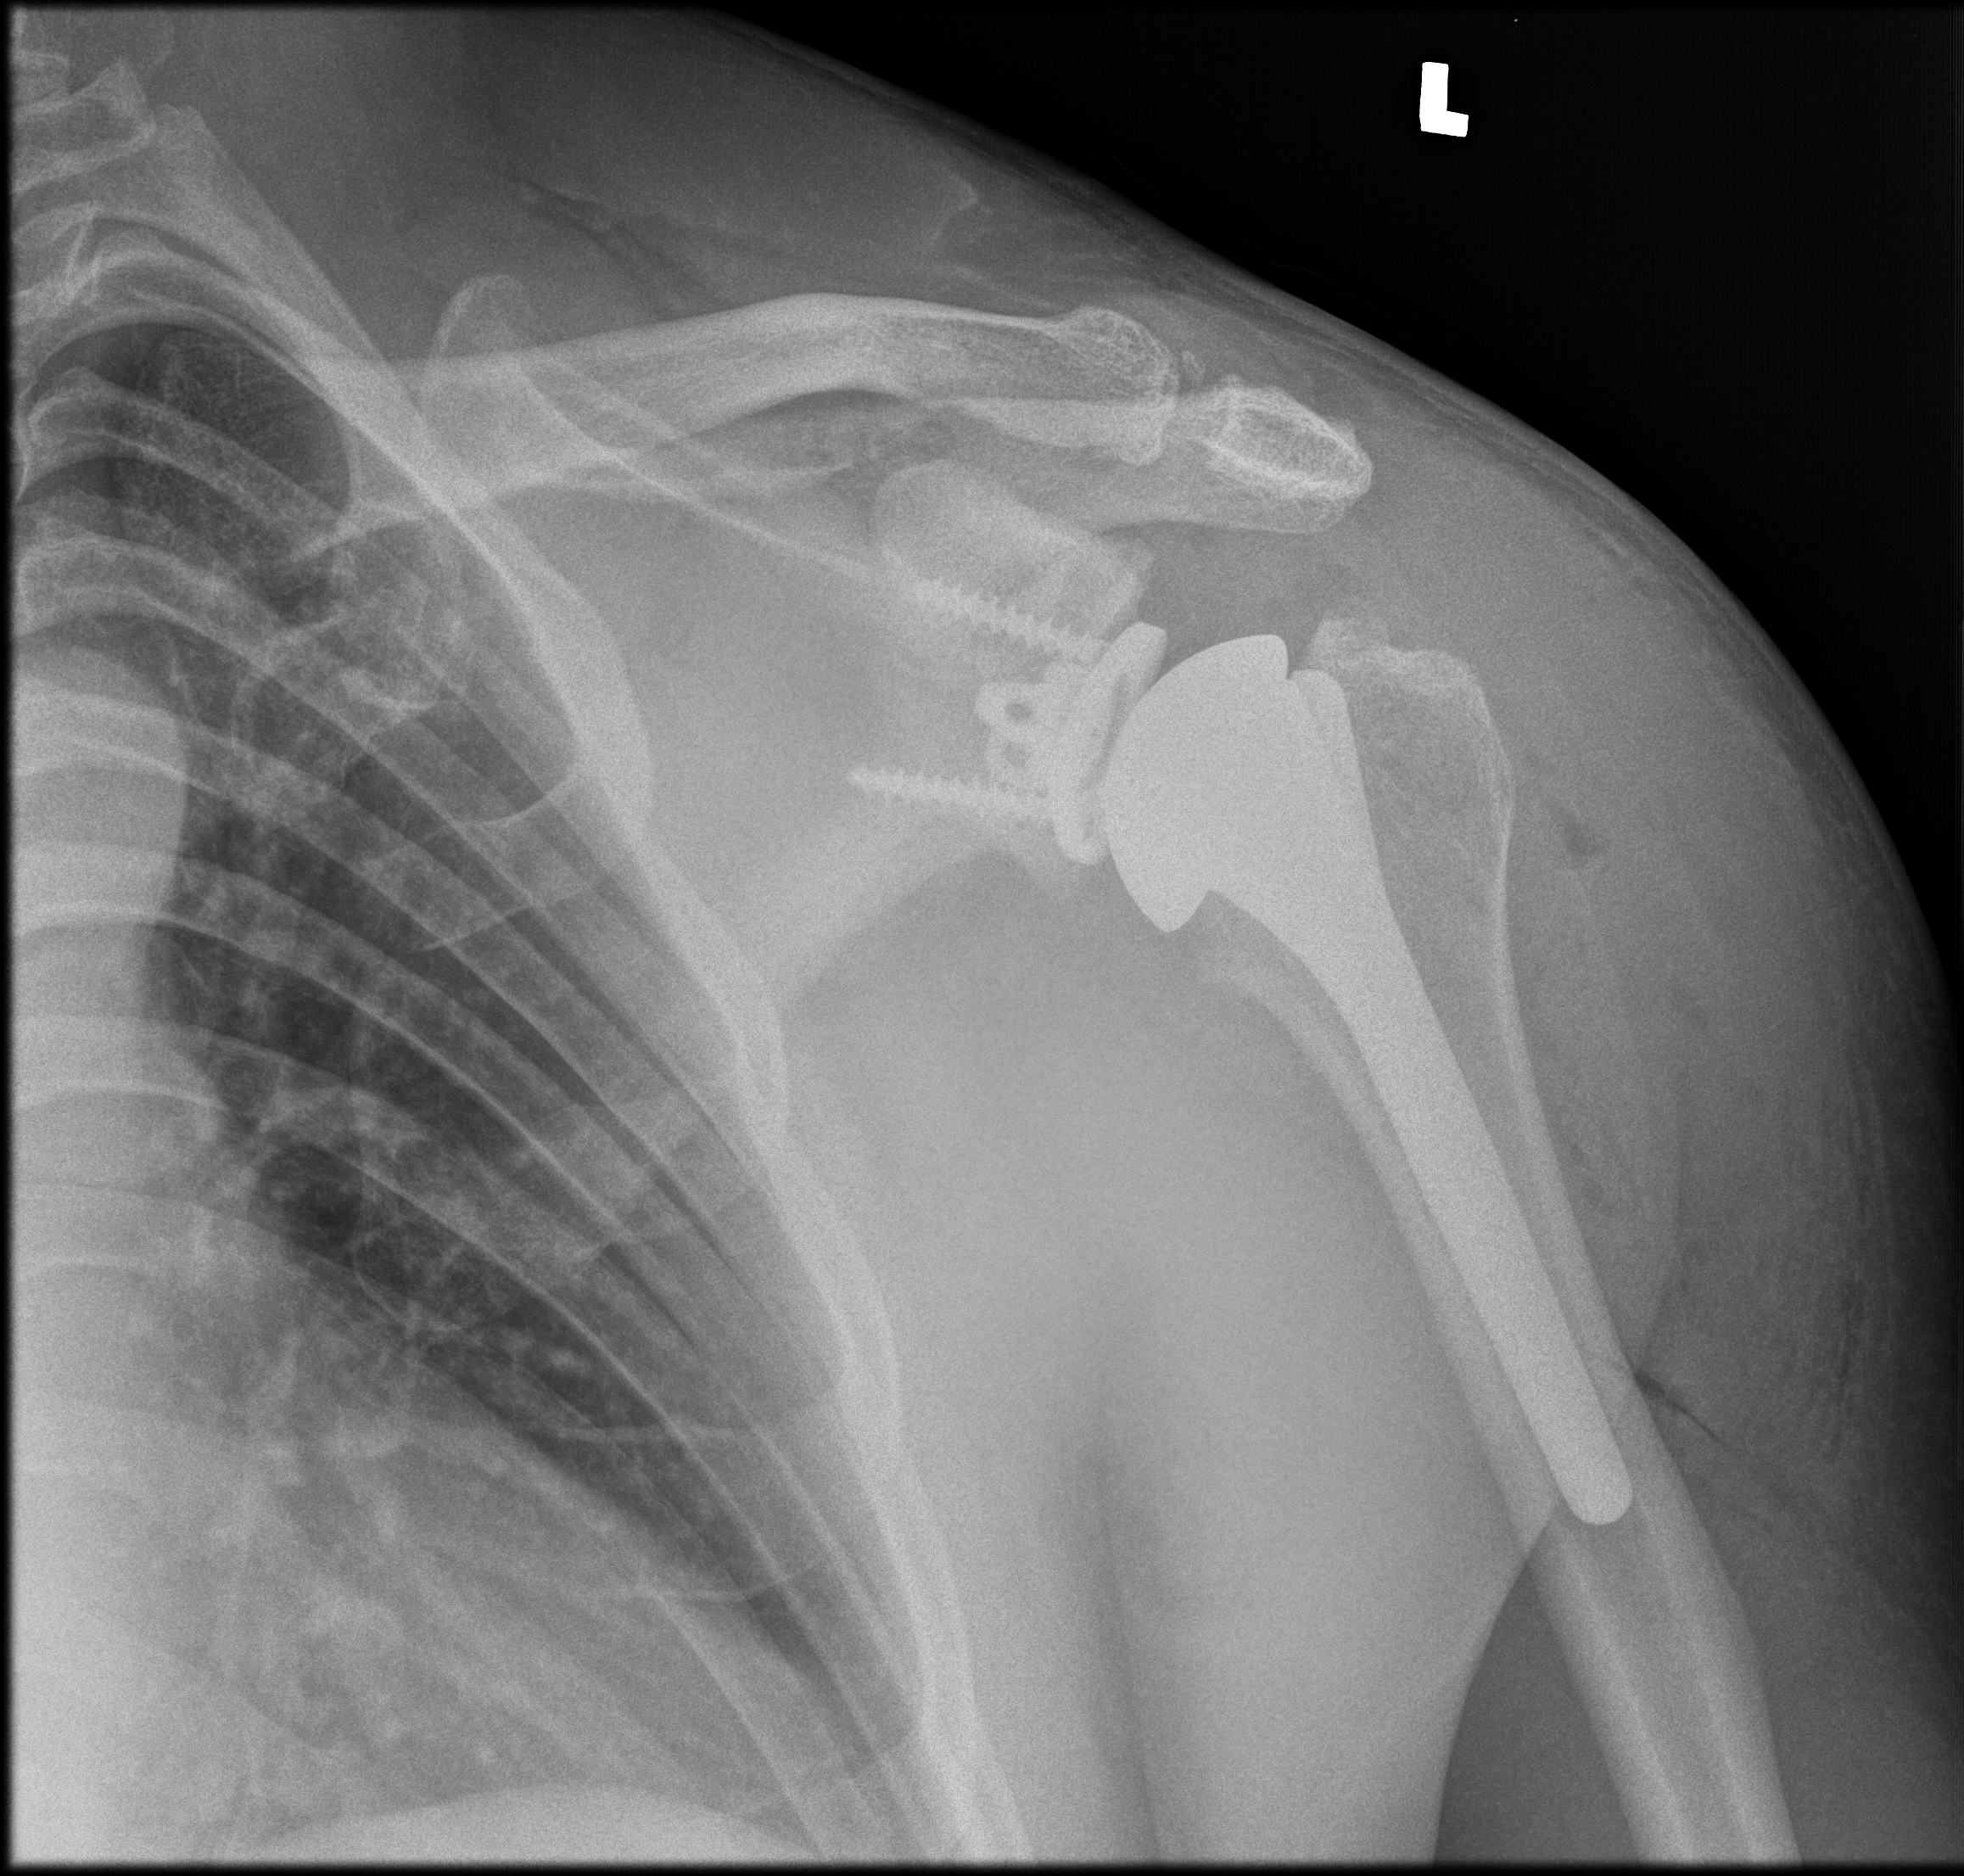

Obecnie istnieją programy komputerowe, które ułatwiają planowanie zabiegów operacyjnych. Procedura ta obejmuje przeprowadzenie tomografii komputerowej chorego stawu ramieniowego przed zabiegiem. Następnie wyniki badania są importowane do specjalnego oprogramowania, które generuje trójwymiarowy model operowanego stawu. Programy te oferują zestaw narzędzi, które umożliwiają precyzyjne zaplanowanie pozycji implantów oraz ich rozmiarów. W znacznym stopniu ułatwiają one przeprowadzenie zabiegu operacyjnego oraz zmniejszają ryzyko popełnienia błędu.

Obecnie technologia medyczna stale się rozwija. Niektóre firmy integrują planowanie z samym zabiegiem operacyjnym. Oznacza to, że podczas zabiegu ortopeda jest prowadzony przez system nawigacyjny wspomagany komputerowo. Jednakże, jeśli chodzi o protezy stawu ramieniowego, według mojej oceny, są one wciąż uznawane za produkt jeszcze nie do końca doskonały.